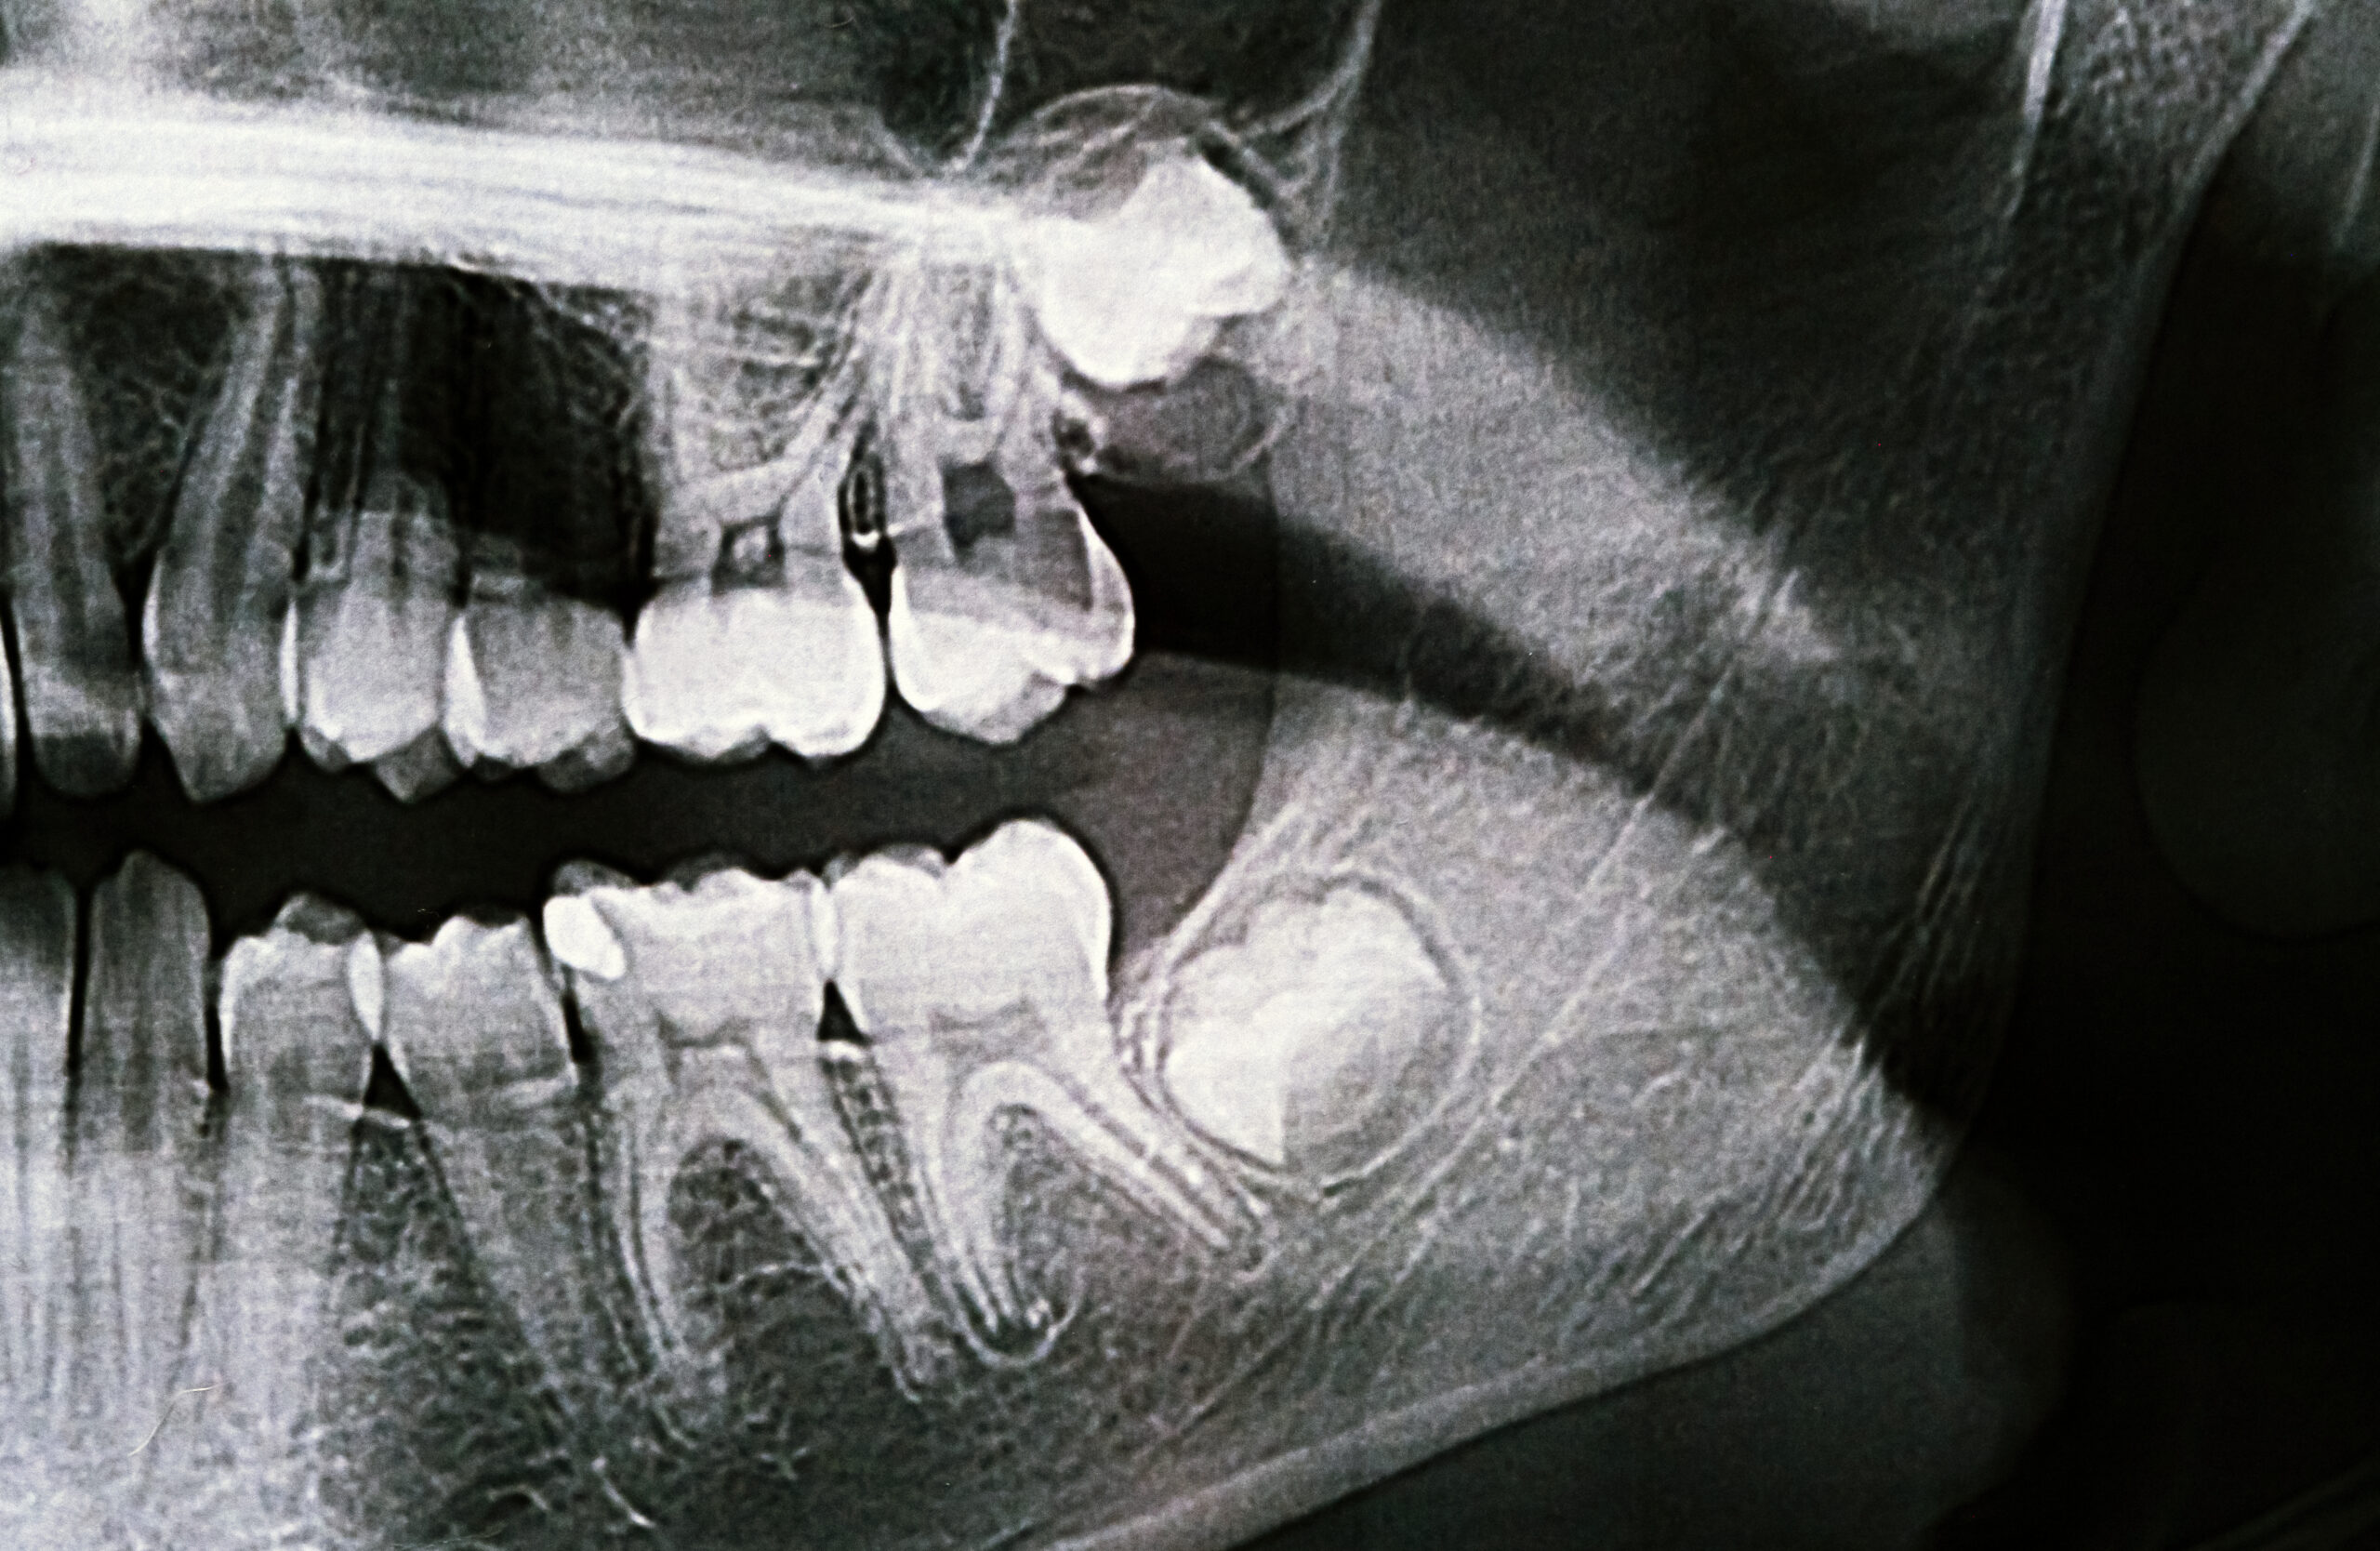

This condition most commonly involves lower wisdom teeth, as they frequently erupt incompletely or at an unfavorable angle. Limited access for cleaning allows inflammation and infection to develop quickly in the surrounding gingival tissues.

Pericoronitis usually occurs when a wisdom tooth cannot fully erupt into the oral cavity. The remaining gum tissue forms a pocket that traps bacteria and irritants.

Contributing factors include poor oral hygiene, impacted or partially impacted third molars, trauma caused by contact with the opposing tooth, and temporary immune system changes. Together, these factors allow inflammation to persist and increase the risk of infection.